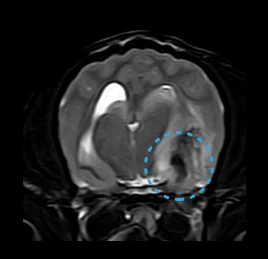

• 뇌종양

• 뇌출혈